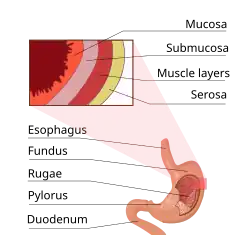

Structure

In the human digestive system, the stomach lies between the esophagus and the duodenum (the first part of the small intestine). It is in the left upper quadrant of the abdominal cavity. The top of the stomach lies against the diaphragm. Lying behind the stomach is the pancreas. A large double fold of visceral peritoneum called the greater omentum hangs down from the greater curvature of the stomach. Two sphincters keep the contents of the stomach contained; the lower esophageal sphincter (found in the cardiac region), at the junction of the esophagus and stomach, and the pyloric sphincter at the junction of the stomach with the duodenum.

Sections

The human stomach can be divided into four sections, beginning at the cardia followed by the fundus, the body and the pylorus.[9][10]

- The gastric cardia is where the contents of the esophagus empty from the gastroesophageal sphincter into the cardiac orifice, the opening into the gastric cardia.[11][10] A cardiac notch at the left of the cardiac orifice, marks the beginning of the greater curvature of the stomach. A horizontal line across from the cardiac notch gives the dome-shaped region called the fundus.[10] The cardia is a very small region of the stomach that surrounds the esophageal opening.[10]

- The fundus (from Latin 'bottom') is formed in the upper curved part.[12]

- The body or corpus is the main, central region of the stomach.[12]

- The pylorus (from Greek 'gatekeeper') connects the stomach to the duodenum at the pyloric sphincter. The pyloric antrum opens to the body of the stomach.[12]

Wall

Like the other parts of the gastrointestinal wall, the human stomach wall from inner to outer, consists of a mucosa, submucosa, muscular layer, subserosa and serosa.[19]

The inner part of the stomach wall is the gastric mucosa a mucous membrane that forms the lining of the stomach. The membrane consists of an outer layer of columnar epithelium, a lamina propria, and a thin layer of smooth muscle called the muscularis mucosa. Beneath the mucosa lies the submucosa, consisting of fibrous connective tissue.[20] Meissner's plexus is in this layer interior to the oblique muscle layer.[21]

Outside of the submucosa lies the muscular layer. It consists of three layers of muscular fibres, with fibres lying at angles to each other. These are the inner oblique, middle circular, and outer longitudinal layers.[22] The presence of the inner oblique layer is distinct from other parts of the gastrointestinal tract, which do not possess this layer.[23] The stomach contains the thickest muscular layer consisting of three layers, thus maximum peristalsis occurs here.